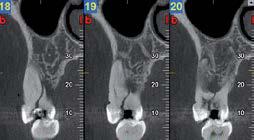

L’innovazione e la sicurezza sono due dei valori perseguiti dallo Studio Braconi a Terni, un punto di riferimento nell’ambito della radiologia 3D ortopedica grazie alla presenza del macchinario Newton 5G XL: si tratta dell’unico apparecchio nel Centro Italia che permette di eseguire una perfetta diagnostica per immagini in ortopedia e per la cervicale, oltre per le piccole articolazioni come seni paranasali, orecchie, colonna cervicale, gomito, polso, mano, ginocchio, caviglia e piede.

Nell’ambito della radiologia 3D ortopedica, il centro diagnostico utilizza il nuovissimo macchinario NewTom 5G XL, in grado di individuare con la massima precisione la presenza di fratture o lussazioni delle articolazioni, controllare la corretta guarigione di una frattura, valutare una lesione o una ferita causata da infezione, artrite o crescita anormale dell’osso.

Il tutto mediante una semplice e veloce scansione, grazie alla quale si otterranno diverse immagini in 3D ad altissima risoluzione e, per ottenere immagini ancora più nitide mediante un bassissimo dosaggio di radiazioni, gli esperti si avvalgono dell’innovazione racchiusa nella tecnologia Cone Beam.

Se con la radiologia tradizionale era necessario eseguire scansioni multiple, la novità introdotta dal macchinario NewTom 5G XL risiede nella capacità di fornire immagini ad alta risoluzione in un’unica scansione, mostrando nitidamente i dettagli delle articolazioni degli arti superiori e inferiori. Inoltre, a differenza della tecnologia 2D, la radiologia 3D ortopedica permette di individuare immediatamente alcune patologie come quella del metatarso, la quale richiede un allineamento visivo dedicato o una diagnosi delle micro fratture ossee.